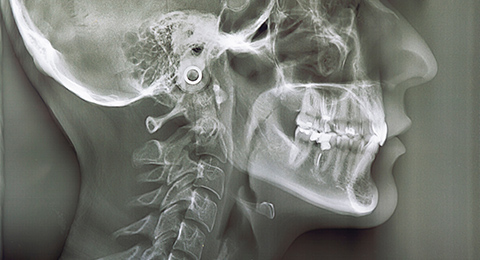

治療の精度を高めるために、当院では歯科用CTやセファロ、iTero Elementなどの先端機器を用いた精密検査を行っています。歯並びや骨格、噛み合わせなどを立体的に把握し、歯の動きを正確にシミュレーションしながら、緻密な治療プランを作成します。高精度な検査と丁寧なカウンセリングで、安心して治療を始められるようサポートいたします。